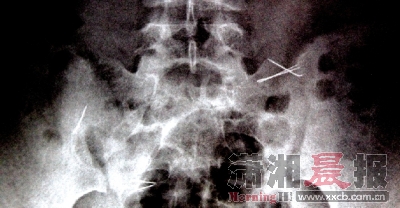

ทั้งนี้ เหตุการณ์ดังกล่าวเกิดขึ้นเมื่อช่วงเช้าของวันที่ 8 ตุลาคม โดยเด็กหญิงเสี่ยวหยุน (นามสมมติ) วัย 13 ปี ซึ่งอาศัยอยู่กับคุณยายที่เมืองจูโจว มณฑลหูหนาน ได้กลืนเข็มเย็บผ้าลงท้อง คุณยายจึงรีบพาเธอส่งโรงพยาบาลอย่างเร่งด่วน โดยแพทย์ได้ใช้เวลาผ่าตัดนานกว่า 4 ชั่วโมง จึงสามารถนำเศษเข็มเย็บผ้า 2 อัน ขนาดประมาณ 2 เซนติเมตร ที่อยู่ในลำไส้เล็กออกมาได้ ซึ่งการผ่าตัดครั้งนี้ต้องใช้ความระมัดระวังอย่างสูง เพราะหากผิดพลาดอาจทำให้กระเพาะอาหาร หรือลำไส้ทะลุได้ อย่างไรก็ตาม ยังคงเหลือเศษเข็มเย็บผ้าเล็ก ๆ อีก 4 ชิ้น ในลำไส้ใหญ่ ซึ่งแพทย์แนะนำให้เสี่ยวหยุนทานผักกุยช่าย และผักโขม เพื่อจะได้ขับถ่ายออกมาทางอุจจาระ